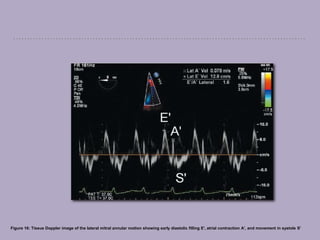

Tissue Doppler echocardiography

Tissue doppler echocardiography (TDE) uses the Doppler frequency shift to calculate

low myocardial velocity, to objectively quantify regional myocardial motion.

Pulsed TDE is similar to PWD, while the color-coded TDE display is based on

assigning colors to different velocities.

Lower velocity colors tend to be darker colors, while higher velocities are

represented by brighter colors.

This modality has been applied in the assessment of regional and global left

ventricular systolic and diastolic function.

TDE is limited by its reliance on the angle of interrogation.

Figure 16: Tissue Doppler image of the lateral mitral annular motion showing early diastolic filling E', atrial contraction A', and movement in systole S'